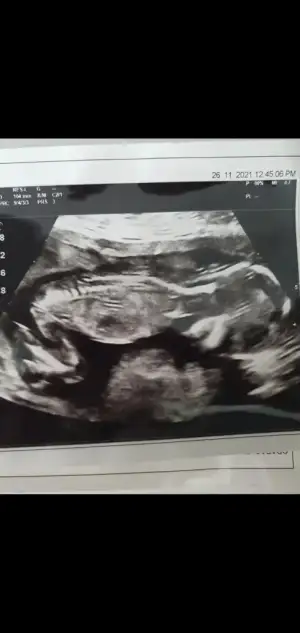

Kizlar mesela bu ultrason gecenki randevumdan. Burda bariz kasilma var. Sadece bebegin ayaklarini oynatacak yeri var. Kafasi ve govdesi sıkışmıs durumda. Hem bebek rahat hareket edemiyo ve kasilmasan dolayi suyuda az oluyomus. Boyle devam ederse erken dogum riski olur dedi. Bu yuzden bol istirahat ve bol su ic dedi drum.

Eklentiler

• Screenshot_20211209-192151_Gallery.webp

Screenshot_20211209-192151_Gallery.webp

15,4 KB · Görüntüleme: 69